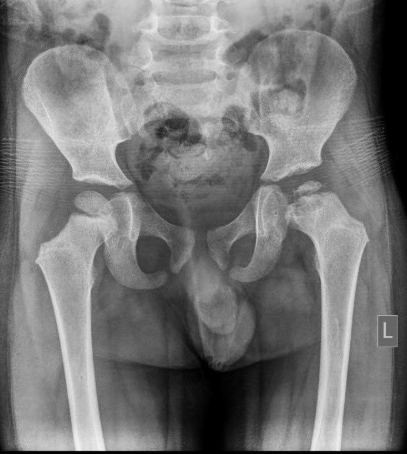

Not so Hip

An 18-year-old male presented to the Emergency Department after a motor vehicle collision at unknown speeds. Patient was the restrained driver, airbags did deploy, and he’s unsure if he lost consciousness. He is primarily complaining of bilateral hip and right hand pain with notable obligate abduction and external rotation of the right lower extremity on initial inspection.